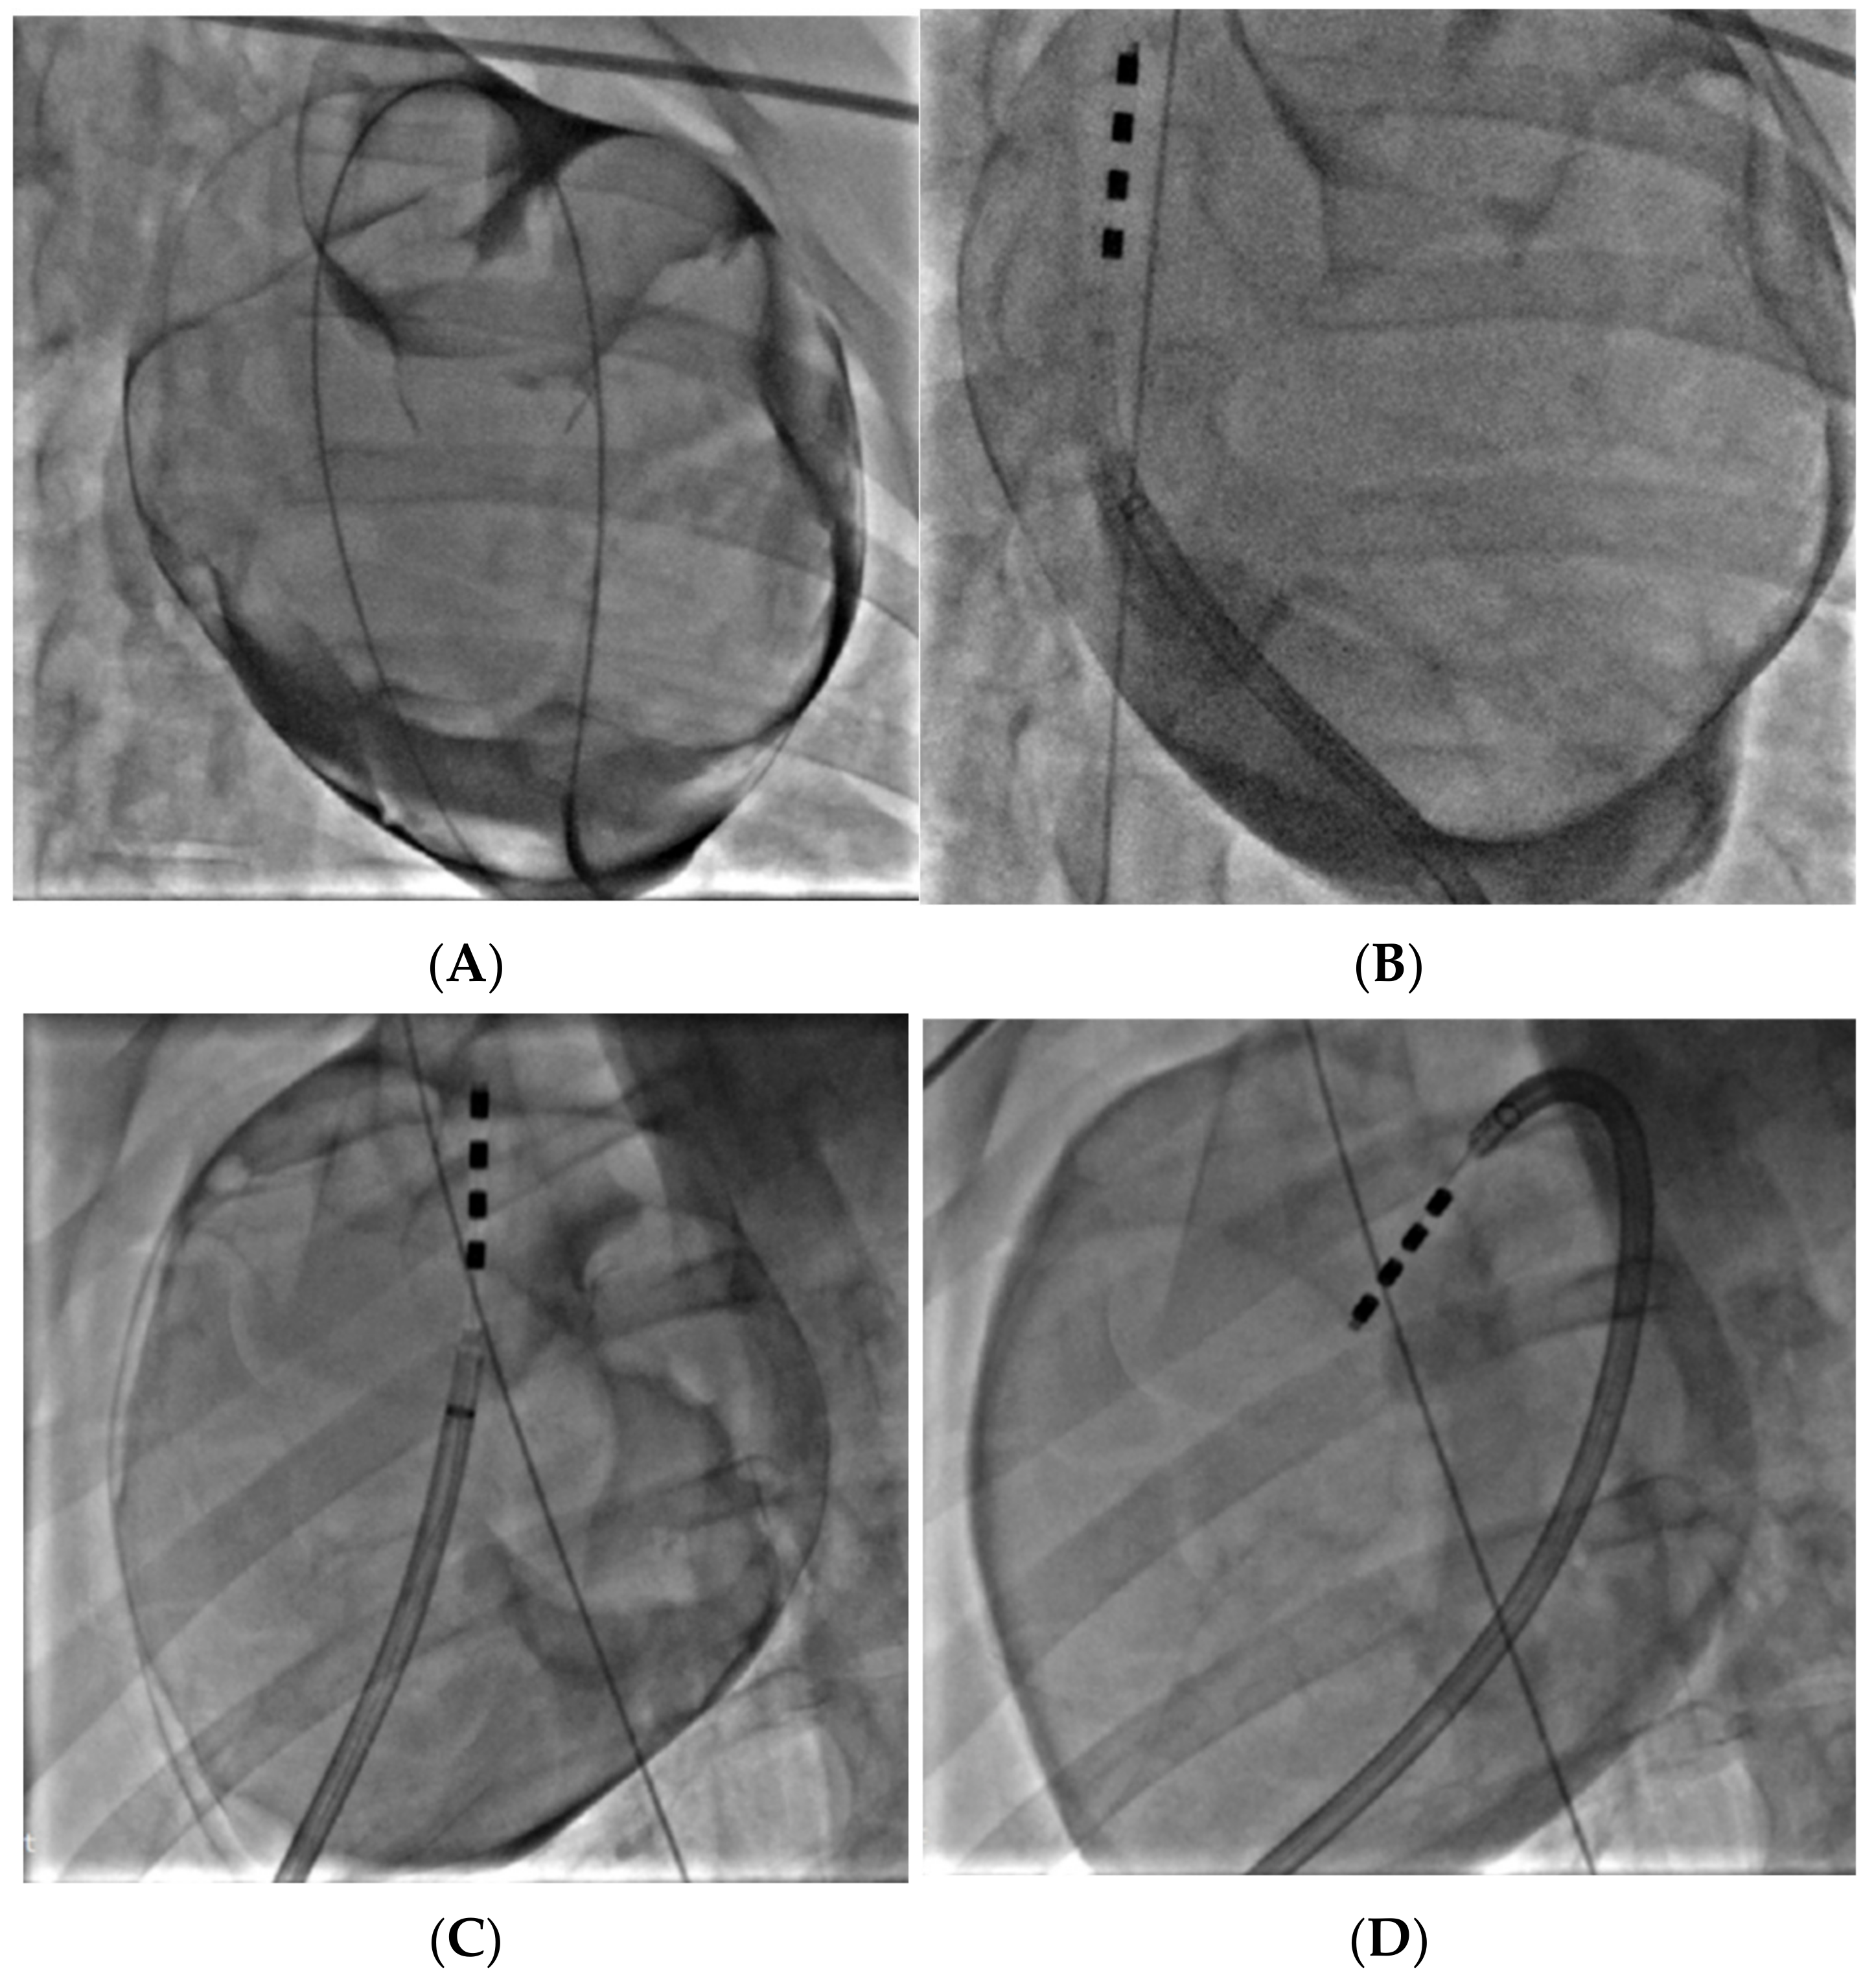

2.5. Porcine Study—Catheter Access and Navigation

3.4. Porcine Study—Catheter Access and Navigation